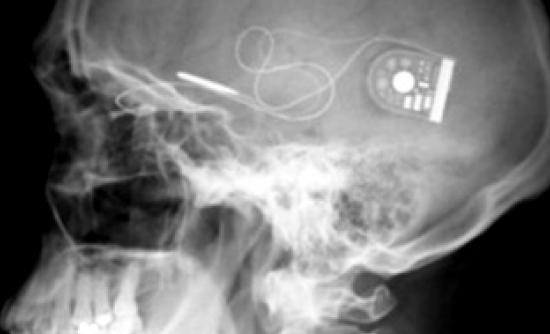

Με μια πρωτοποριακή χειρουργική μέθοδο δυο Βρετανοί που ήταν πλήρως τυφλοί, κατάφεραν να ανακτήσουν την όραση τους. Τους εμφύτευσαν στον αμφιβληστροειδή ένα ειδικό ηλεκτρονικό τσιπ, και πλέον μπορούν να αντιλαμβάνονται το φως αλλά και να ξεχωρίζουν τα σχήματα στον χώρο.Σύμφωνα με το iatropedia.gr, η επέμβαση έγινε στο οφθαλμολογικό νοσοκομείο της Οξφόρδης από την ομάδα του καθηγητή Robert Mac Laren, και ο ένας από τους 2 ασθενείς είναι Ελληνικής καταγωγής. Και οι 2 ασθενείς είχαν χάσει την όραση τους από μια σπάνια ασθένεια των οφθαλμών, την μελαγχρωστική αμφιβληστροειδοπάθεια. Σε αυτή την ασθένεια παύουν να λειτουργούν σταδιακά, τα κύτταρα φωτουποδοχείς στο πίσω μέρος του ματιού.Το απίστευτα λεπτό και μικρό τσιπ που τοποθετήθηκε στο πίσω μέρος του ματιού των 2 ασθενών ανέλαβε να κάνει ακριβώς αυτή τη δουλειά. Τα 1500 φωτοευαίσθητα pixels, που έχει πάνω του, παίζουν πλέον τον ρόλο των ράβδων και των κώνων. Το φως που μπαίνει στο μάτι διεγείρει τα pixels, έτσι το μάτι το αντιλαμβάνεται, και στέλνει μήνυμα στο οπτικό νεύρο και από εκεί στον εγκέφαλο.Ο καθηγητής Mac Laren τονίζει ότι: «είναι η πρώτη φορά που με την βοήθεια της τεχνολογίας καταφέραμε να επανενεργοποιήσουμε τον αμφιβληστροειδή, σε ανθρώπους που ήταν εντελώς τυφλοί. Πλέον μπορούν να αντιλαμβάνονται το φως που μπαίνει μέσα από το παράθυρο, καθώς και διάφορα σχήματα. Μπορούν επίσης να ξεχωρίζουν τα έπιπλα και που βρίσκεται η πόρτα. Μέχρι στιγμής τα βλέπουν όλα ασπρόμαυρα αλλά είμαστε αισιόδοξοι ότι θα καταφέρουμε να τα βλέπουν και έγχρωμα…»Μέχρι στιγμής οι επιστήμονες τονίζουν ότι το συγκεκριμένο τσιπ μπορεί να ανακουφίσει ανθρώπους με την συγκεκριμένη ασθένεια και όχι εκείνους που πάσχουν από γλαύκωμα, ή νόσους του οπτικού νεύρου, ή την εκφύλιση της ωχράς κηλίδας.